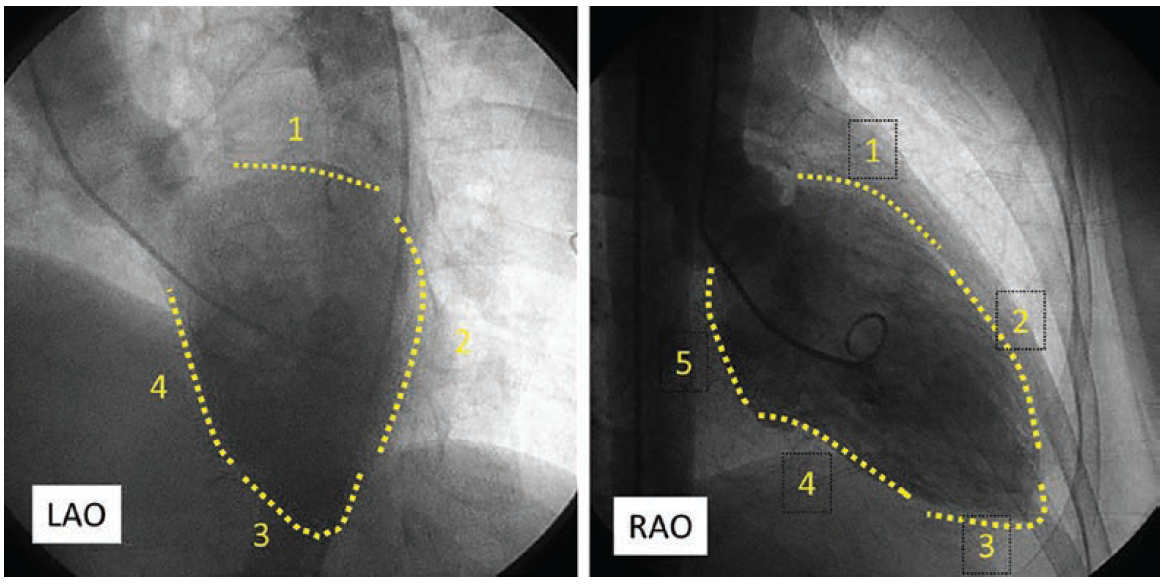

LV Angiography and the Oblique Views

The oblique angulations are also critical to our appreciation of ventriculography as well as a chest roentgenology. Figure 10 shows cineframes of left ventriculograms in the left anterior oblique view and the right anterior oblique views. When injecting the LV during ventriculography, in the LAO with cranial projection, we see the heart on end with the segments of the LV wall numbered (Figure 10 legend). In the RAO view, the heart is elongated. The 5 segments of the LV are used to describe wall motion and LV contraction (1 = basal anterior; 2 = anterior; 3 = apical; 4 = inferior, and 5 = inferior basal at the plane of the mitral valve). For a quick reference, the LV shape can easily be recalled by remembering hand position in Figure 2. This is an easy method to remember the heart shape and can then be applied to the chest x-ray.